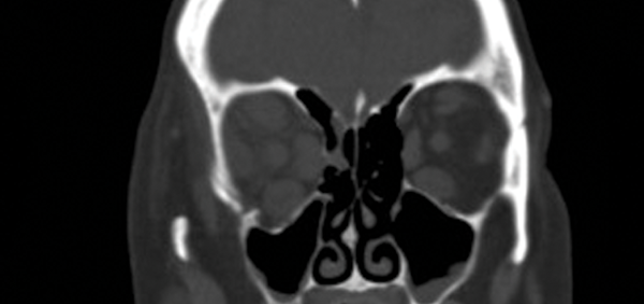

Cortical blindness

Shampa Gupta

JVK Sardar

1st August 2014

Education

Case Reports